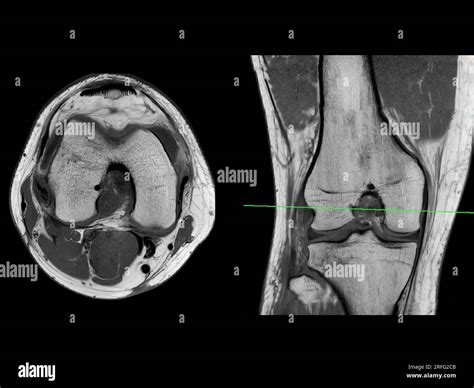

Understand your health with our expert guide to interpreting Knee MRI images. We break down common scan findings, including meniscus tears, ligament injuries, and cartilage damage. Learn what your radiology report means, how diagnostic imaging aids treatment planning, and what to expect during your orthopedic scan to ensure better recovery outcomes for your joint health.